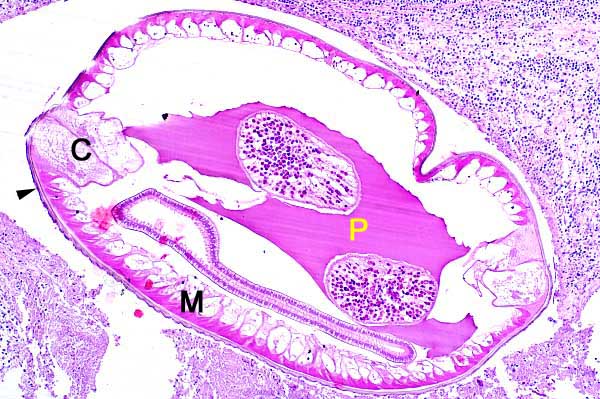

The nematode has a thick smooth pigmented cuticle (arrowhead), coelomyarian-polymyarian musculature (M), prominent and dissimilar lateral cords (C) and a pseudocoelom (P) containing small amounts of eosinophilic material.